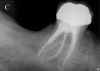

Figure 4a  Initially, the periapical radiographs showed the root fractures but not the extent of the lingual fracture or the alveolar complications (A,B).

Figure 4a

Figure 4b  Initially, the periapical radiographs showed the root fractures but not the extent of the lingual fracture or the alveolar complications (A,B).

Figure 4b

Initially, case studies appeared in the endodontic literature in which patients underwent CBCT imaging for the purposes of diagnosis20-22 and presurgical treatment planning.19 Recent reports have successfully shown the use of CBCT to locate missed canals,23 detect the extent of dentoalveolar fractures,20 identify resorption patterns,22 and compare cystic with granulomatous periapical lesions.17 Figure 2A through Figure 2C show a case in which the missed canal was suggested by periapical radiographs but confirmed with CBCT.24 Similarly in Figure 3A through Figure 3D, the additional diagnostic information attained from CBCT confirmed the diagnosis and extent of the root fracture, which initially was observed in the periapical radiographs (Figure 4A and Figure 4B).20 Notably, the extent of the lingual fracture as well as any alveolar complications could be visualized by CBCT only.